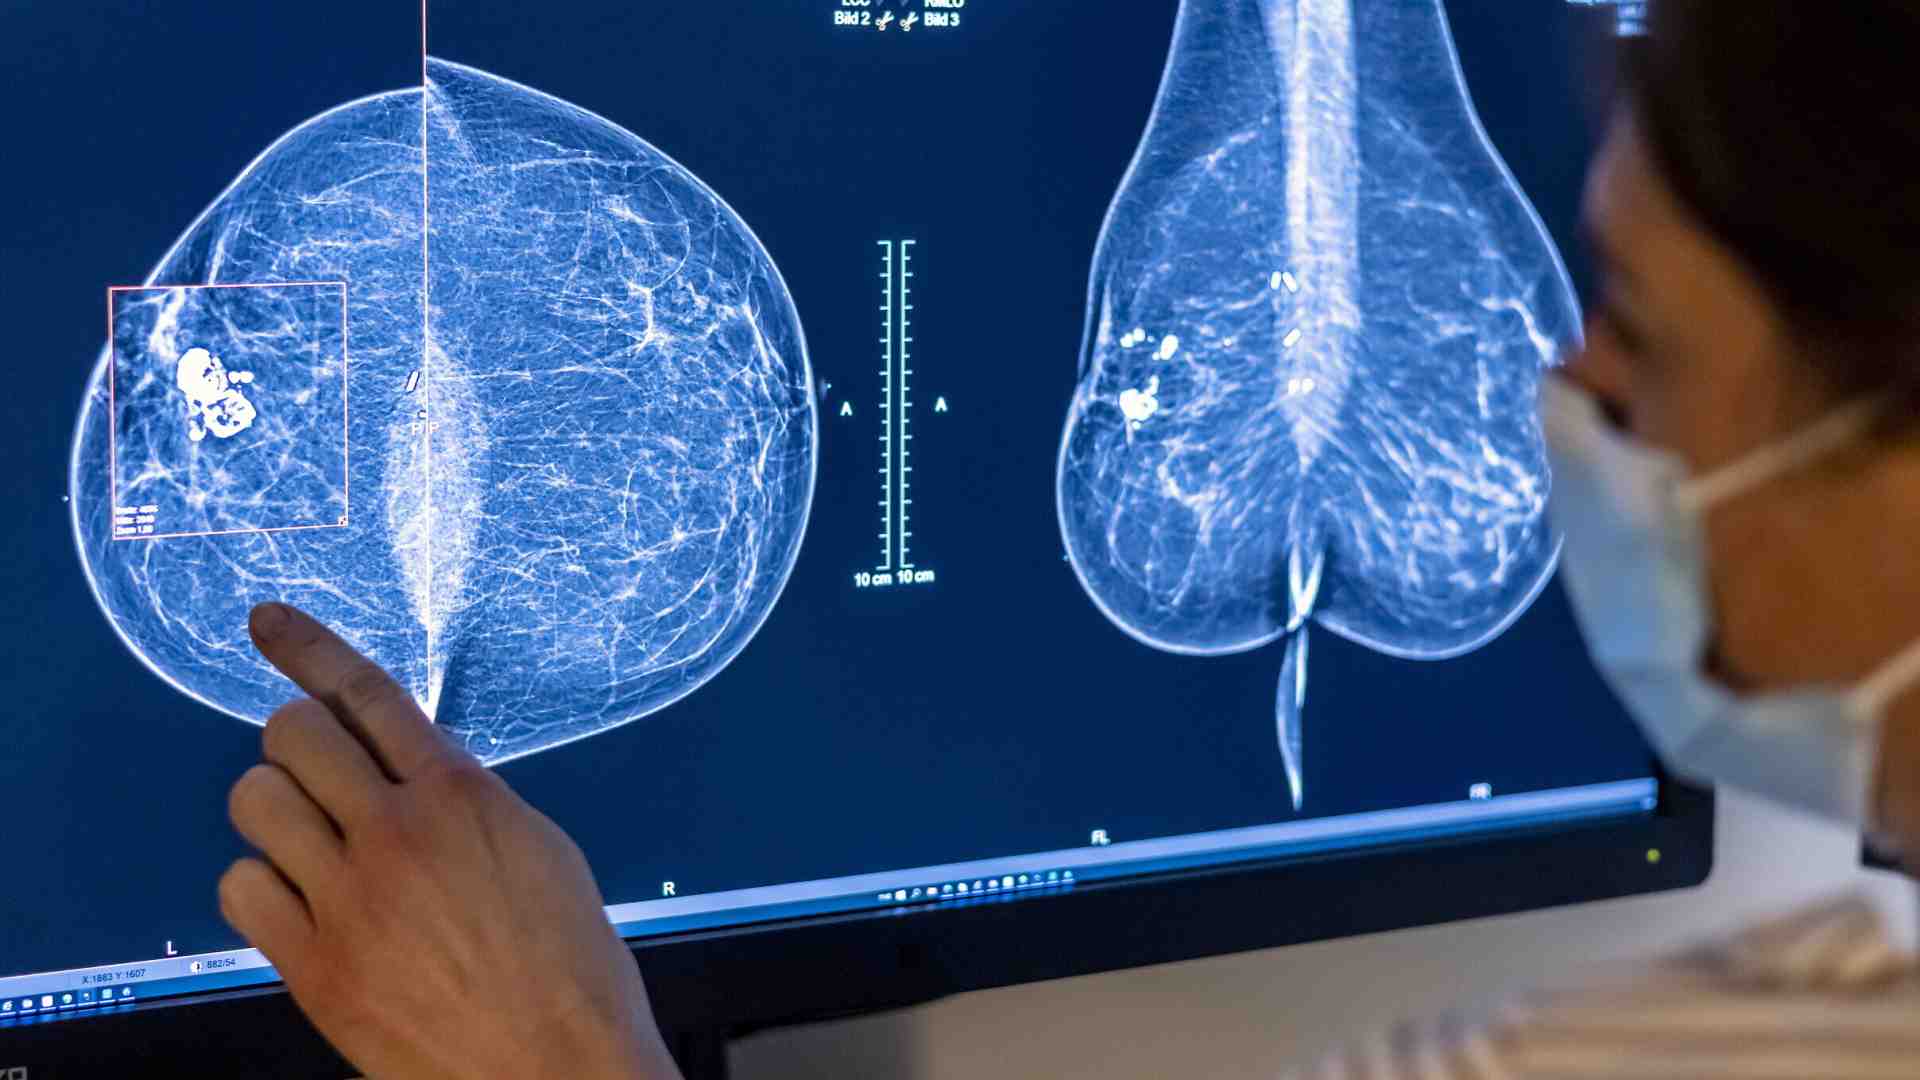

L'intelligenza artificiale (IA) non è solo quella generativa, che negli ultimi tempi ha attirato l'attenzione del pubblico con la creazione di immagini, testi e video. Da molti anni, l'IA è utilizzata in ambiti ove suscita meno clamore, ma estremamente rilevanti, come la classificazione e la diagnosi medica. Sistemi avanzati di IA sono stati progressivamente integrati nei processi diagnostici, dimostrando capacità sempre maggiori nell'identificare anomalie spesso invisibili all'occhio umano. In particolare, la diagnostica per immagini rappresenta uno dei settori dove l'IA ha avuto un impatto significativo, supportando i medici nell'interpretazione delle immagini e migliorando la precisione e la rapidità delle diagnosi.

In questo contesto si inserisce un recente studio appena pubblicato su Nature Medicine, che analizza come l'IA possa essere utilizzata per migliorare lo screening mammografico e il rilevamento del cancro al seno. Questo studio è stato condotto in Germania e ha coinvolto oltre 460.000 donne, con l'obiettivo di valutare l'efficacia di un sistema IA nel supportare i radiologi durante la doppia lettura delle mammografie, un processo essenziale per garantire la qualità degli screening. I risultati mostrano che l'IA ha permesso di scoprire più tumori senza aumentare inutilmente i falsi allarmi, riducendo anche il carico di lavoro per i radiologi.

Il parametro più significativo analizzato nello studio è stato il tasso di rilevamento del cancro al seno, che misura quanti casi di cancro sono stati diagnosticati ogni 1.000 donne sottoposte a screening. Nel gruppo in cui i radiologi hanno utilizzato il supporto dell’IA, sono stati individuati 6,7 casi su 1.000 donne, rispetto ai 5,7 casi del gruppo che ha seguito il metodo tradizionale. Questo significa che l'IA ha contribuito a identificare un caso in più ogni 1.000 donne, un miglioramento del 17,6%. Diagnosticare un cancro precocemente può essere fondamentale per salvare vite, consentendo trattamenti più tempestivi e meno invasivi.